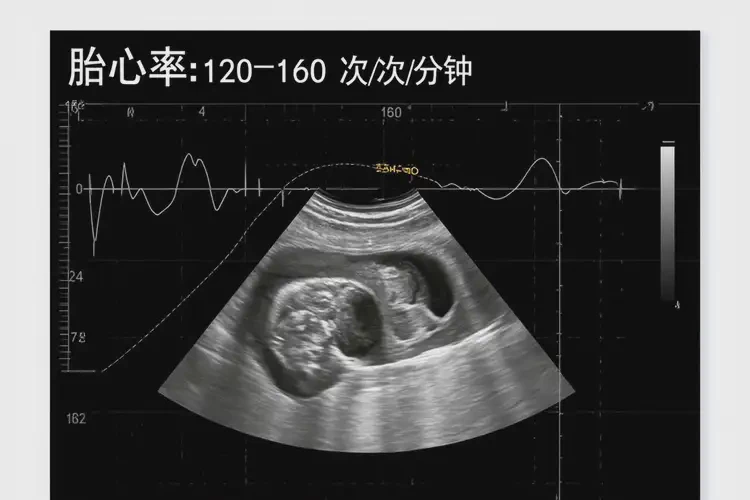

2. 中期胎心率:在懷孕12-20周時(shí),胎心率的正常范圍是120-160次/分鐘。此時(shí),胎心率相對(duì)穩(wěn)定,但仍需定期監(jiān)測(cè)。

3. 晚期胎心率:在懷孕20周以后,胎心率的正常范圍仍然是120-160次/分鐘。此時(shí),胎心率的波動(dòng)可能會(huì)減少,但仍需注意異常情況。

懷孕10多天胎心100多寶寶還能要嗎(圖1)